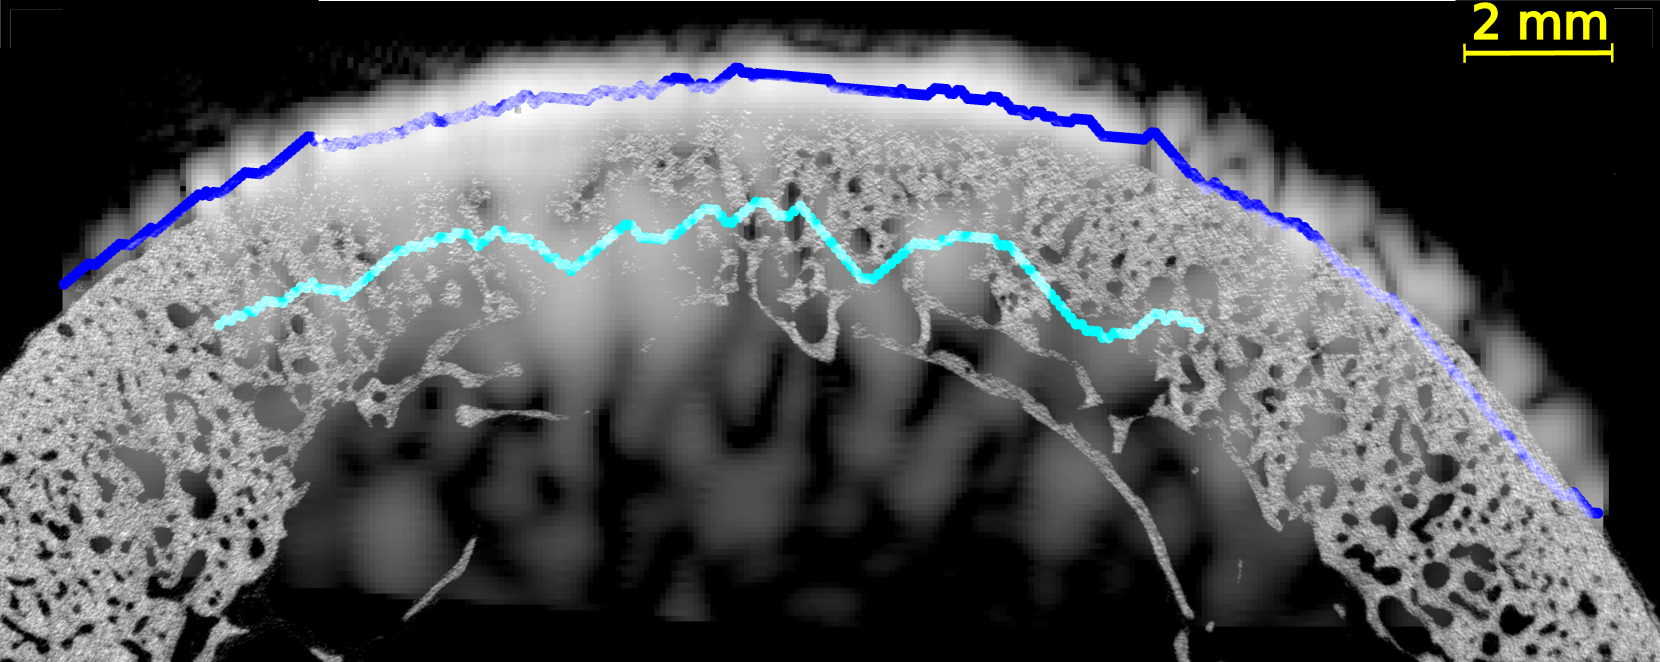

In all US images (Figure 4 and Figures S2-5 of supplementary materials), the periosteal surface appeared as a very bright line. The brightness of the endosteal surface was found to decrease with increasing porosity and with the presence of large pores. The endosteal surface was relatively bright in Samples 1 and 2 which had a small number of large pores and a small porosity; while the contrast of the endosteal surface was relatively weak in Samples 3 and 5 which had a higher porosity and some large pores near the endosteal surface (see the HR-µCT images (panels (a), (d), (g) and (j) of Figure 4). Segmentation with Dijkstra’s algorithm successfully delineated periosteal and endosteal surfaces for all measurement zones in all samples (see Figure 4). US images were aligned on HR-µCT images based on the periosteal surface segmentation. Periosteal surfaces from the US images accurately matched the periosteal surfaces segmented from the HR-µCT images: for all VOIs and all measurement repetitions, the root mean square error (RMSE) between the two segmentations was smaller than 0.3 mm, which value corresponds to half a US wavelength in water at 2.5 MHz (i.e., approximately the resolution limit).

We observed a good match between the segmented endosteal surface in the US image and the boundary of the cortex as seen in the HR-µCT image. The segmented endosteal surface closely followed the shape of the bone in the samples 1 and 2 which were the less porous and less heterogeneous. It is noteworthy that, despite the large thickness and complex geometry of sample 2, the endosteal surface was very bright in the US image. In the more porous and heterogeneous samples 3 and 5, the segmented endosteal surface followed the gross shape of the bone but was inside the cortex as seen in the HR-µCT image, above some large pores found close to the endosteal cortex boundary.

3.4 Ultrasound measurement of cortical thickness.

US imaging could accurately determine the cortical thickness for samples 1 and 2 (across the 4 VOIs, the relative error, compared to the HR-µCT reference, was between 2 and 16 % and between 3 and 11 %, respectively) and less accurately for samples 3 and 5 (across the 4 VOIs, the relative error was between 31 and 34 % and between 45 and 49 %, respectively) (Figure 5). Except for the thickest sample (sample 2, which had a more complex geometry), US underestimated the thickness obtained from HR-µCT images.

We evaluated the quality of US anatomical reconstructions and wave speed measurements across sixteen VOIs from bones of four individuals. Indeed, the bone of a fifth individual (sample 4) was too porous and heterogeneous to be effectively imaged through US. Our results indicate that the cortex boundaries and cortical thickness can be accurately determined for homogeneous and moderately porous VOIs, even for a thick cortex, as observed in samples 1 and 2 (mean thickness 2.9 and 5.9 mm and porosity between 5.0 and 12.3%, respectively). In these cases, the overlaying of US and HR-CT images showed that the segmentation of the surfaces in US images with the Dijkstra’s method closely aligns with the actual boundary, achieving thickness measurements with mean relative errors of 9 % and 4 %, respectively. In regions with higher porosity and larger pore diameters (samples 3 and 5 with porosity between 10.9 and 16.6% and Lg.Po.Dm between 224 and 307 m, respectively), the brightness of the endosteal surface is significantly reduced (from 7 dB to -5 dB). Nevertheless, Dijkstra’s algorithm was able to delineate endosteal boundaries that generally lied within the cortex, above the region with very large pores nearest to the endosteal surface. Consequently, in these cases, US-based cortical thickness measurements underestimated the reference (mean relative errors of 32 % and 47 %). However, for these highly remodeled bones with large resorption cavities leading to a trabecularization of the endosteal region, the delineation of the endosteal boundary as the end of the cortex and the beginning of the medullary canal is ambiguous, making it challenging to obtain a meaningful estimate of cortical thickness in the HR-CT images [5]. Another limiting factor in comparing cortical thicknesses determined from HR-CT and from US images lies in the slight differences in the regions of interest used for each VOI. The region of interest used for HR-CT images (Figure 2) were slightly larger than that used for US images. In the latter, as shown in Figure 4, the surfaces could only be reconstructed for a limited portion of the cortex due to the finite US probe aperture.

In US imaging, any error in the assumed wave speed used for image reconstruction process results in a misplacement of the reconstructed surface positions (shortly, surface position is obtained from the product of an echo time with wave speed). This is why in our imaging approach, the wave speed is determined in bone and soft tissues for each measurement in order to accurately reconstruct bone geometry [20]. In the present study we found that the endosteal surfaces reconstructed from US images closely aligned with the actual surfaces position observed in HR-CT images (Figure 4). This provides further evidence that the wave speed determined by the autofocus method closely approximated the true wave speed.